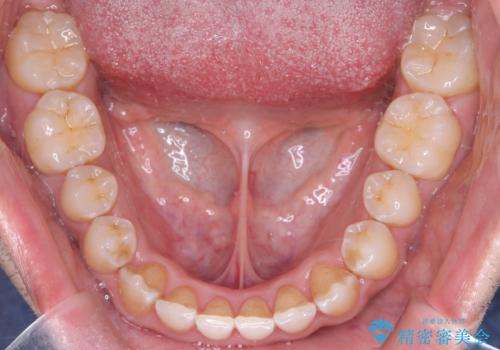

- 左上の八重歯を気にされて来院されました。精密な検査の結果、歯列全体を広げながら八重歯を奥へ移動させることで、美しい歯並びと機能的な咬み合わせが得られると診断。患者様のご希望に合わせ、透明で目立ちにくい**インビザライン(マウスピース矯正)**による治療計画を立案しました。抜歯を避け、歯を少しずつ遠心(奥)へ移動させることで、歯が並ぶスペースを確保し、叢生(歯のデコボコ)を改善します。

今回の矯正治療では、透明なマウスピース型の装置インビザラインを使用しました。この装置は目立ちにくく、取り外しが可能なため、食事や歯磨きも普段通りに行えます。遠心移動という方法で奥歯を後方に動かし、前歯を並べるためのスペースを確保。これにより、抜歯することなく、左上の八重歯を含む叢生を効果的に改善し、整った美しい歯並びと良好な咬み合わせを獲得していただけました。